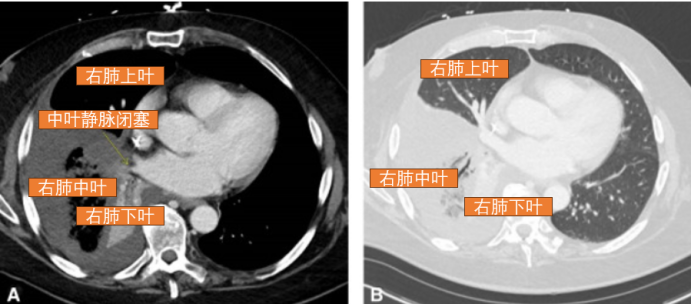

支气管镜检查结果见图6,结果显示左下叶支气管及其段支气管逆时针旋转约150度。

图6 再次入院时支气管镜检查(A示正常解剖结构,B示该患者的解剖结构)